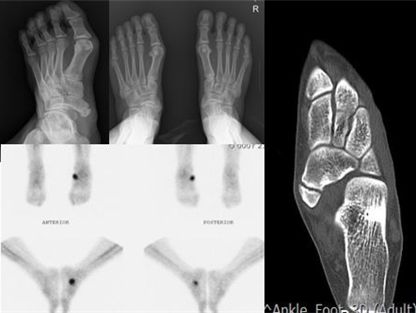

우리나라에서 후천성 평발을 만드는 주된 요인 중의 하나인 부주상골 증후군은 발생 나이 및 치료시작 시기에 따라 치료방법이나 치료성적이 크게 달라질 수 있다. ( 조기 수술이 평발에 중요하다 )

이시기에는 대개 후경골의 이상이 있는 경우가 대부분이어서 수술을 하지 않으면 악화와 호전을 반복하게 되는 것이 일반적인데, 그러다 관절염으로 가는 경우가 많다. 따라서 후경골건의 힘이 살아 있는지 MRI 또는 초음파검사상 이상이 없는지가 중요하고, 이상이 있고 힘이 없으면 또는 평발이 있으면 예후가 좋지 않게 되거나 더 큰 수술을 해야한다. ( 건이전술 및 절골술 ) 수술방법도 수술하는 의사에 따라 여러가지가 있을 수 있다.

이 시기에는 대개 후경골건 부전증이 같이 있으면서 관절염이 동반될 수 있기에 뒷발의 관절염에 대한 수술 즉 관절고정술을 시행하는 것이 건이전술( 힘줄 이식술 )보다 나을 수 있다.